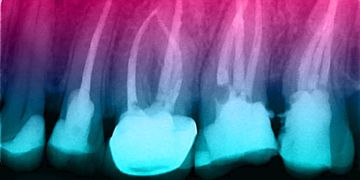

Цикл вебинаров по Эндодонтии

Идея данного онлайн цикла - Алгоритмы принятия клинических решений в эндодонтии.